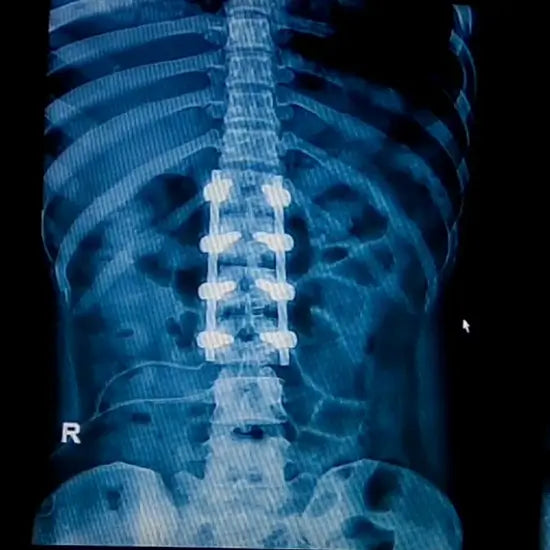

Spinal Stenosis.

What is Lumbar Spinal Stenosis and understand non surgical alternatives

Lumbar spinal stenosis is a disorder that may cause low back and/or leg pain. Lumbar spinal stenosis is a narrowing of the spinal canal in your lower back that may cause pain or numbness in your legs. Its treatment can include physical therapy, medicine, and sometimes surgery. Other modalities, such as Transcutaneous Electrical Nerve Stimulation, Pulsed Electro Magnetic Field Therapy, ultrasound, heat or cold therapy, and traction, can also be effective. PEMF therapy can be effectively used as a drug-free to alleviate spinal stenosis pain. By its very nature, it is based on the principles of low-field magnetic stimulation to promote self-healing in the body. PEMF devices emit pulses at low frequencies, which encourages the stimulation of cells, regenerates affected tissues, and brings relieving effects so that one no longer feels nagging sensations associated with lumbar or cervical stenosis.